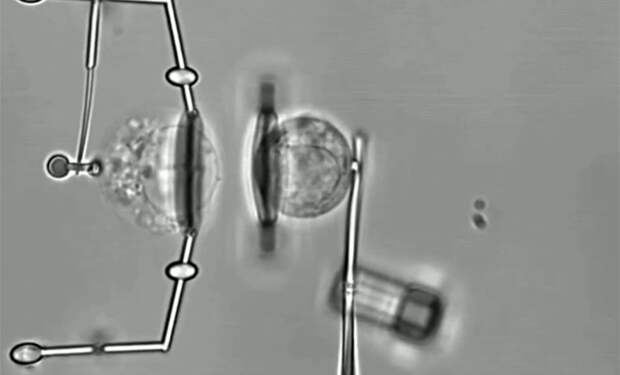

Микроробот состоит из двух частей — магнитного винтообразного наконечника и мягкого эластомерного корпуса. Магнит позволяет управлять движением устройства, направляя его к нужной клетке, а гибкое тело обеспечивает деликатный контакт и захват без повреждения биоматериала. В ходе экспериментов робот успешно выделял и удерживал отдельные клетки, различая здоровые и поврежденные.